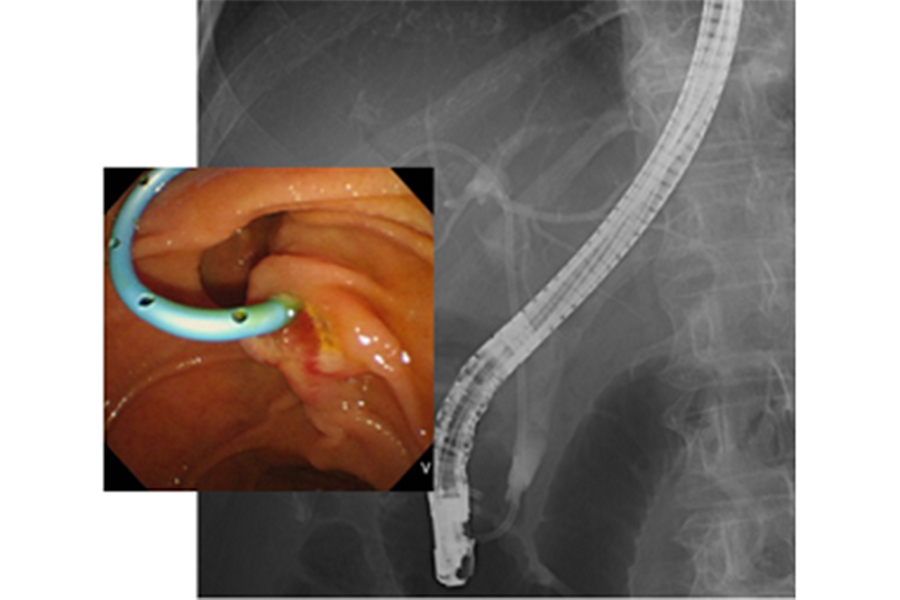

内視鏡的逆行性胆道膵管造影(ERCP)は、内視鏡を口から入れて十二指腸まで進め、胆管や膵管にカテーテルを挿入して造影剤を注入し、胆道・膵管のレントゲン撮影を行う検査です(図1)。

これにより結石や腫瘍といった胆管や胆嚢、膵管の異常を詳しく調べることができます。近年では画像診断の進歩により、超音波検査やCT、MRIでも胆道や膵管の情報が得られるようになってきていますが、悪性の病気が疑われた場合にはERCP実施時に胆道や膵管の細胞や組織を採取して病理検査を行うことがあります。また、胆管・膵管の狭窄に対してプラスチックや金属のステント(筒状のもの)を挿入して、胆汁や膵液の流出障害を改善させる治療を行うことがあるほか(図2)、胆管結石や膵石に対しては内視鏡で取り除く治療も行うことができます(図3)。このようにERCPは胆膵領域の診断、治療に重要な役割を担っています。